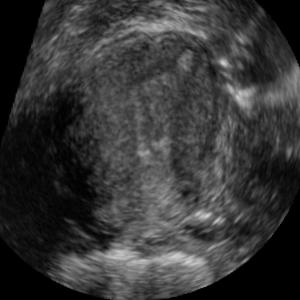

Standard plane (SP) localization is essential in routine clinical ultrasound (US) diagnosis. Compared to 2D US, 3D US can acquire multiple view planes in one scan and provide complete anatomy with the addition of coronal plane. However, manually navigating SPs in 3D US is laborious and biased due to the orientation variability and huge search space. In this study, we introduce a novel reinforcement learning (RL) framework for automatic SP localization in 3D US. Our contribution is three-fold. First, we formulate SP localization in 3D US as a tangent-point-based problem in RL to restructure the action space and significantly reduce the search space. Second, we design an auxiliary task learning strategy to enhance the model's ability to recognize subtle differences crossing Non-SPs and SPs in plane search. Finally, we propose a spatial-anatomical reward to effectively guide learning trajectories by exploiting spatial and anatomical information simultaneously. We explore the efficacy of our approach on localizing four SPs on uterus and fetal brain datasets. The experiments indicate that our approach achieves a high localization accuracy as well as robust performance.